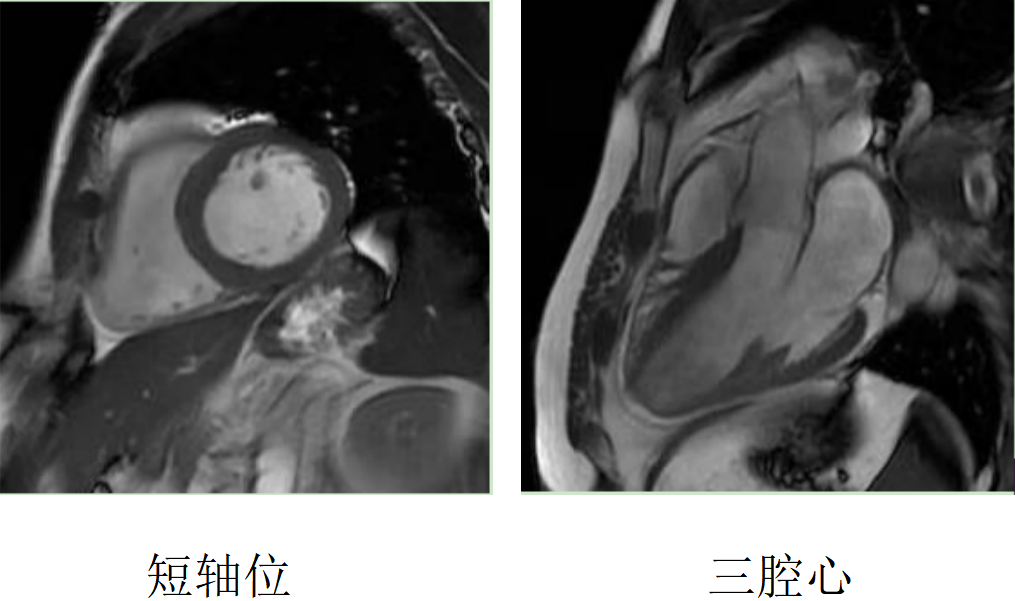

缺血性心肌病:心臟磁共振可以評估心肌活性,心肌組織中失去活性的心肌細胞和延遲強化存在可靠的對應關系,即失去活性的心肌組織有延遲強化,如急性心梗或急性冠脈綜合征、慢性缺血性心肌病。

右冠狀動脈供血區(qū)透壁心梗伴心肌纖化